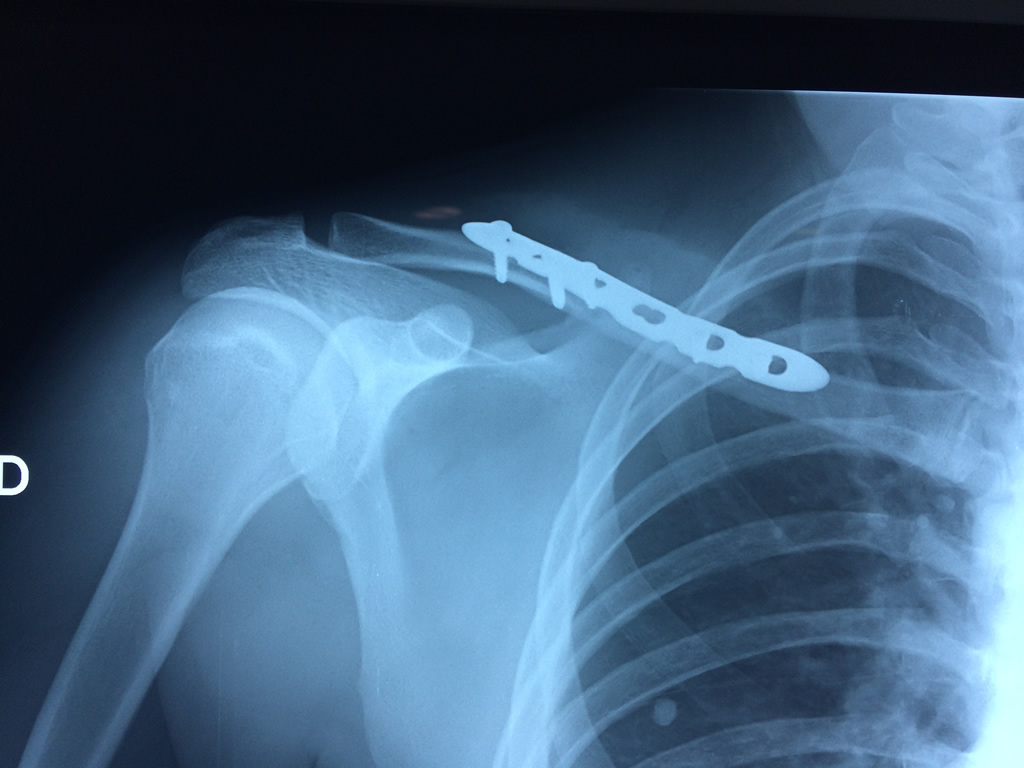

Cirugías de Hombros - Clavícula

La clavícula es un hueso largo, con forma de "S" itálica, situado en la parte anterosuperior del tórax. Junto con la escápula forman la cintura escapular. Se puede palpar por toda su longitud y se extiende del esternón al acromion de la escápula, siguiendo una dirección oblicua lateral y posterior.